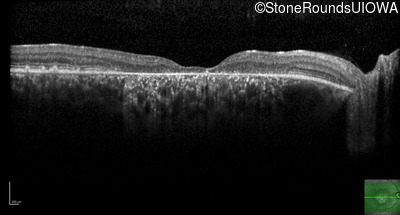

AR Stargardt Disease (IIA)

Age at visit: 35 years

This 35 year old woman first started holding her reading material closer than normal when she was 7 years old.

Diagnosis & molecular findings

AR Stargardt Disease ABCA4 Val1681 del15gctGTGGTTGCCATCTGC Gly1961Glu GGA>GAA AR